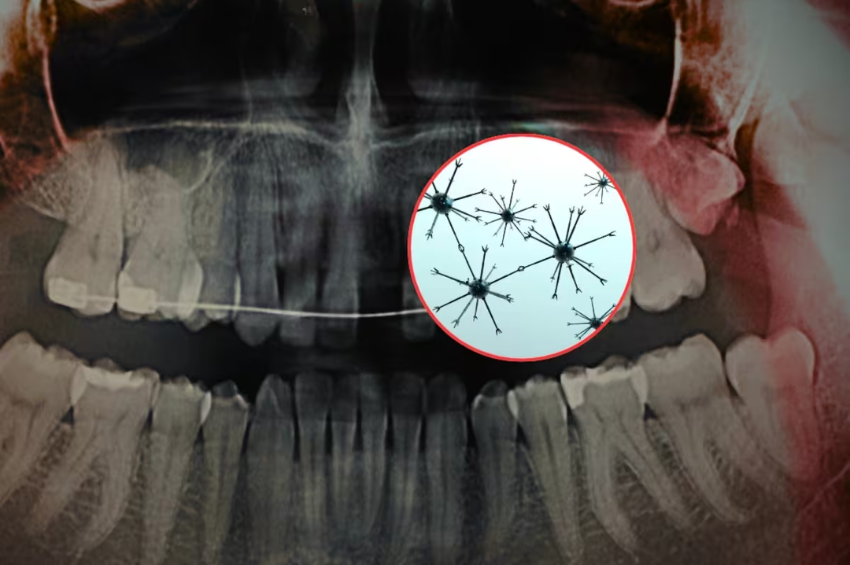

De acuerdo con un estudio publicado en la revista científica Advanced Science y difundido por el Instituto Indio de Ciencias (IISc), en colaboración con la empresa tecnológica Theranautilus, se desarrollaron nanorobots magnéticos llamados Calbots que buscan tratar la sensibilidad dental desde el interior del diente.

Los Calbots son nanorobots magnéticos diseñados para penetrar en los túbulos dentinarios, que son pequeños canales dentro de la dentina que pueden conectar con las terminaciones nerviosas del diente. Cuando estos canales quedan expuestos, se produce la sensibilidad.

Los Calbots miden alrededor de 400 nanómetros y están compuestos por un material biocerámico basado en silicato de calcio. Su funcionamiento se basa en tres pasos principales:

- Guía magnética: se utiliza un campo magnético externo para dirigir los nanorobots hacia los túbulos dentinarios expuestos.

- Penetración profunda: pueden llegar a una profundidad de entre 300 y 500 micrómetros dentro del diente.

- Sellado interno: una vez dentro, se autoensamblan y forman tapones estables similares al cemento, bloqueando los canales que generan la sensibilidad.

Este sellado imita el entorno natural del diente y podría ofrecer un alivio prolongado.